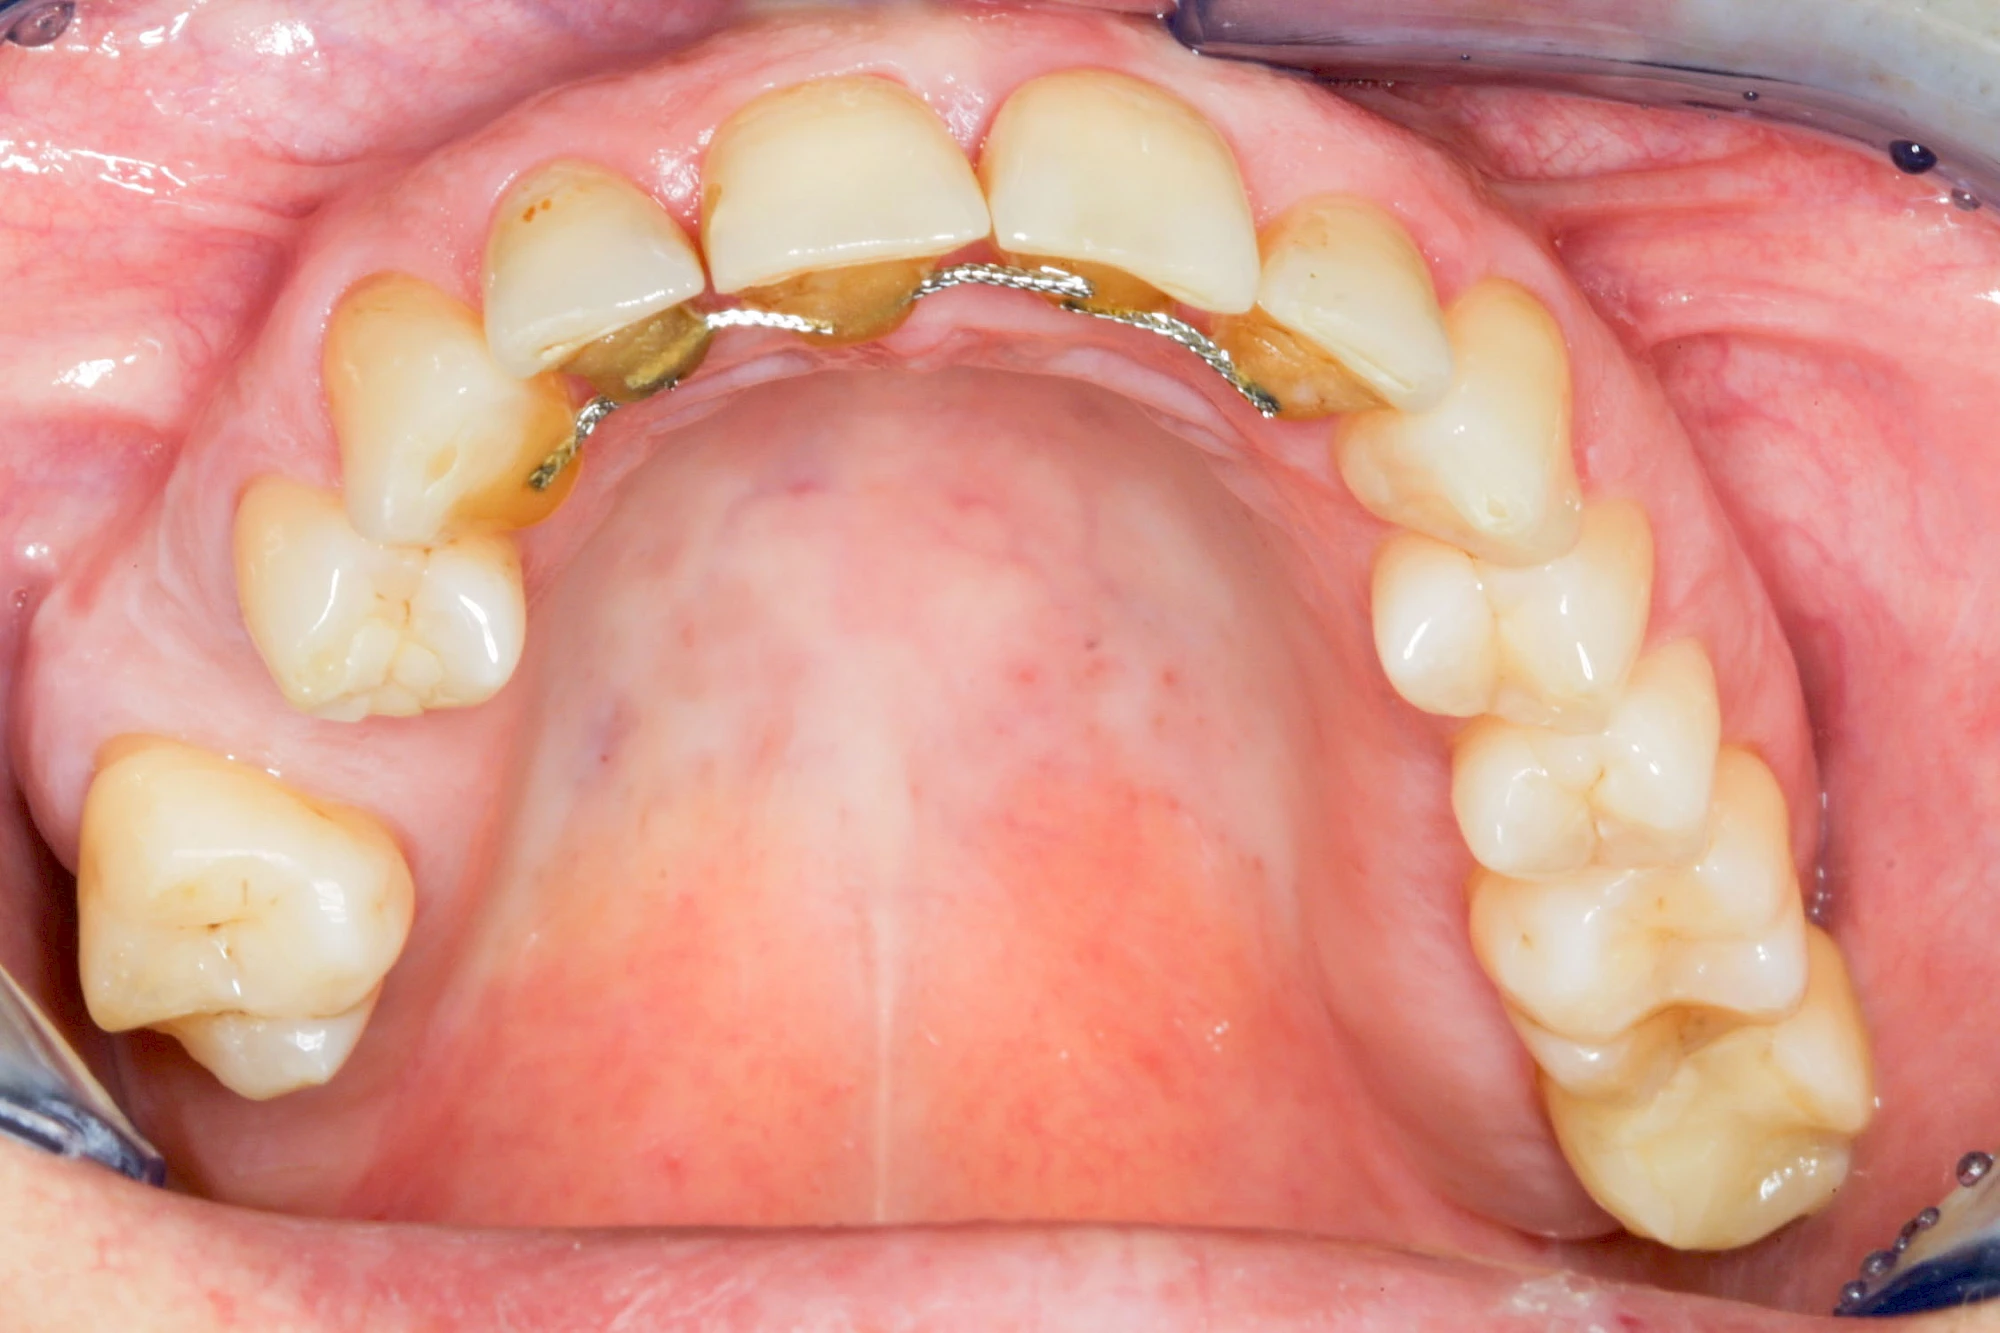

Fehlen einzelne Zähne und die Nachbarzähne sind unbeschadet oder gut zahnärztlich versorgt, werden immer häufiger Implantate gewählt, um die Lücken zu schließen. Auch bei größeren oder verteilten Lücken, wenn keine herausnehmbare Prothese gewünscht ist, werden Implantate für Kronen- bzw. Brückenversorgungen gesetzt. In Einzelfällen entscheiden sich sogar zahnlose Patienten für eine festsitzende Versorgung auf Implantaten.

Varianten zur Verankerung von festsitzendem Zahnersatz auf Implantaten